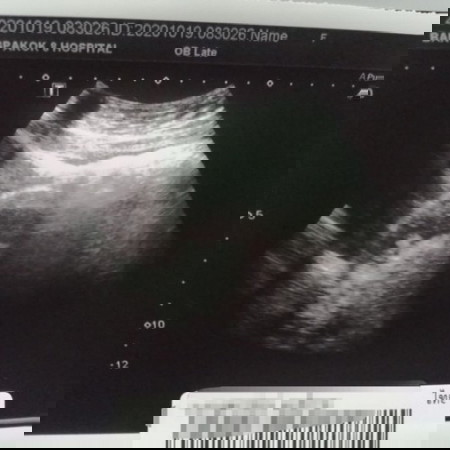

ตรวจเจอเนื้องอกในขณะตั้งครรภ์

แม่ได้ไปอัลตร้าซาวด์4มิติที่คลินิกแห่งนึง ผลปรากฏว่าน้องแข็งแรงดี ทุกอย่างเป็นปกติ แต่แม่มีเนื้องอกที่หน้าผนังมดลูก ซึ่งตกใจเล็กน้อยเพราะหมอที่ฝากครรภ์ไม่ได้กล่าวถึงเรื่องนี้เลย และหมอคลินิกแนะนำว่าหลังคลอดเสร็จ1เดือนให้อัลตร้าซาวด์อีกครั้งเพื่อดู ผลที่ตามมาอาจจะคลอดก่อนกำหนดเพราะเนื้องอกโตตามอายุครรภ์ กำหนดคลอด29พฤษภาคม64 #ขอกำลังใจแม่ๆหน่อยค่ะ